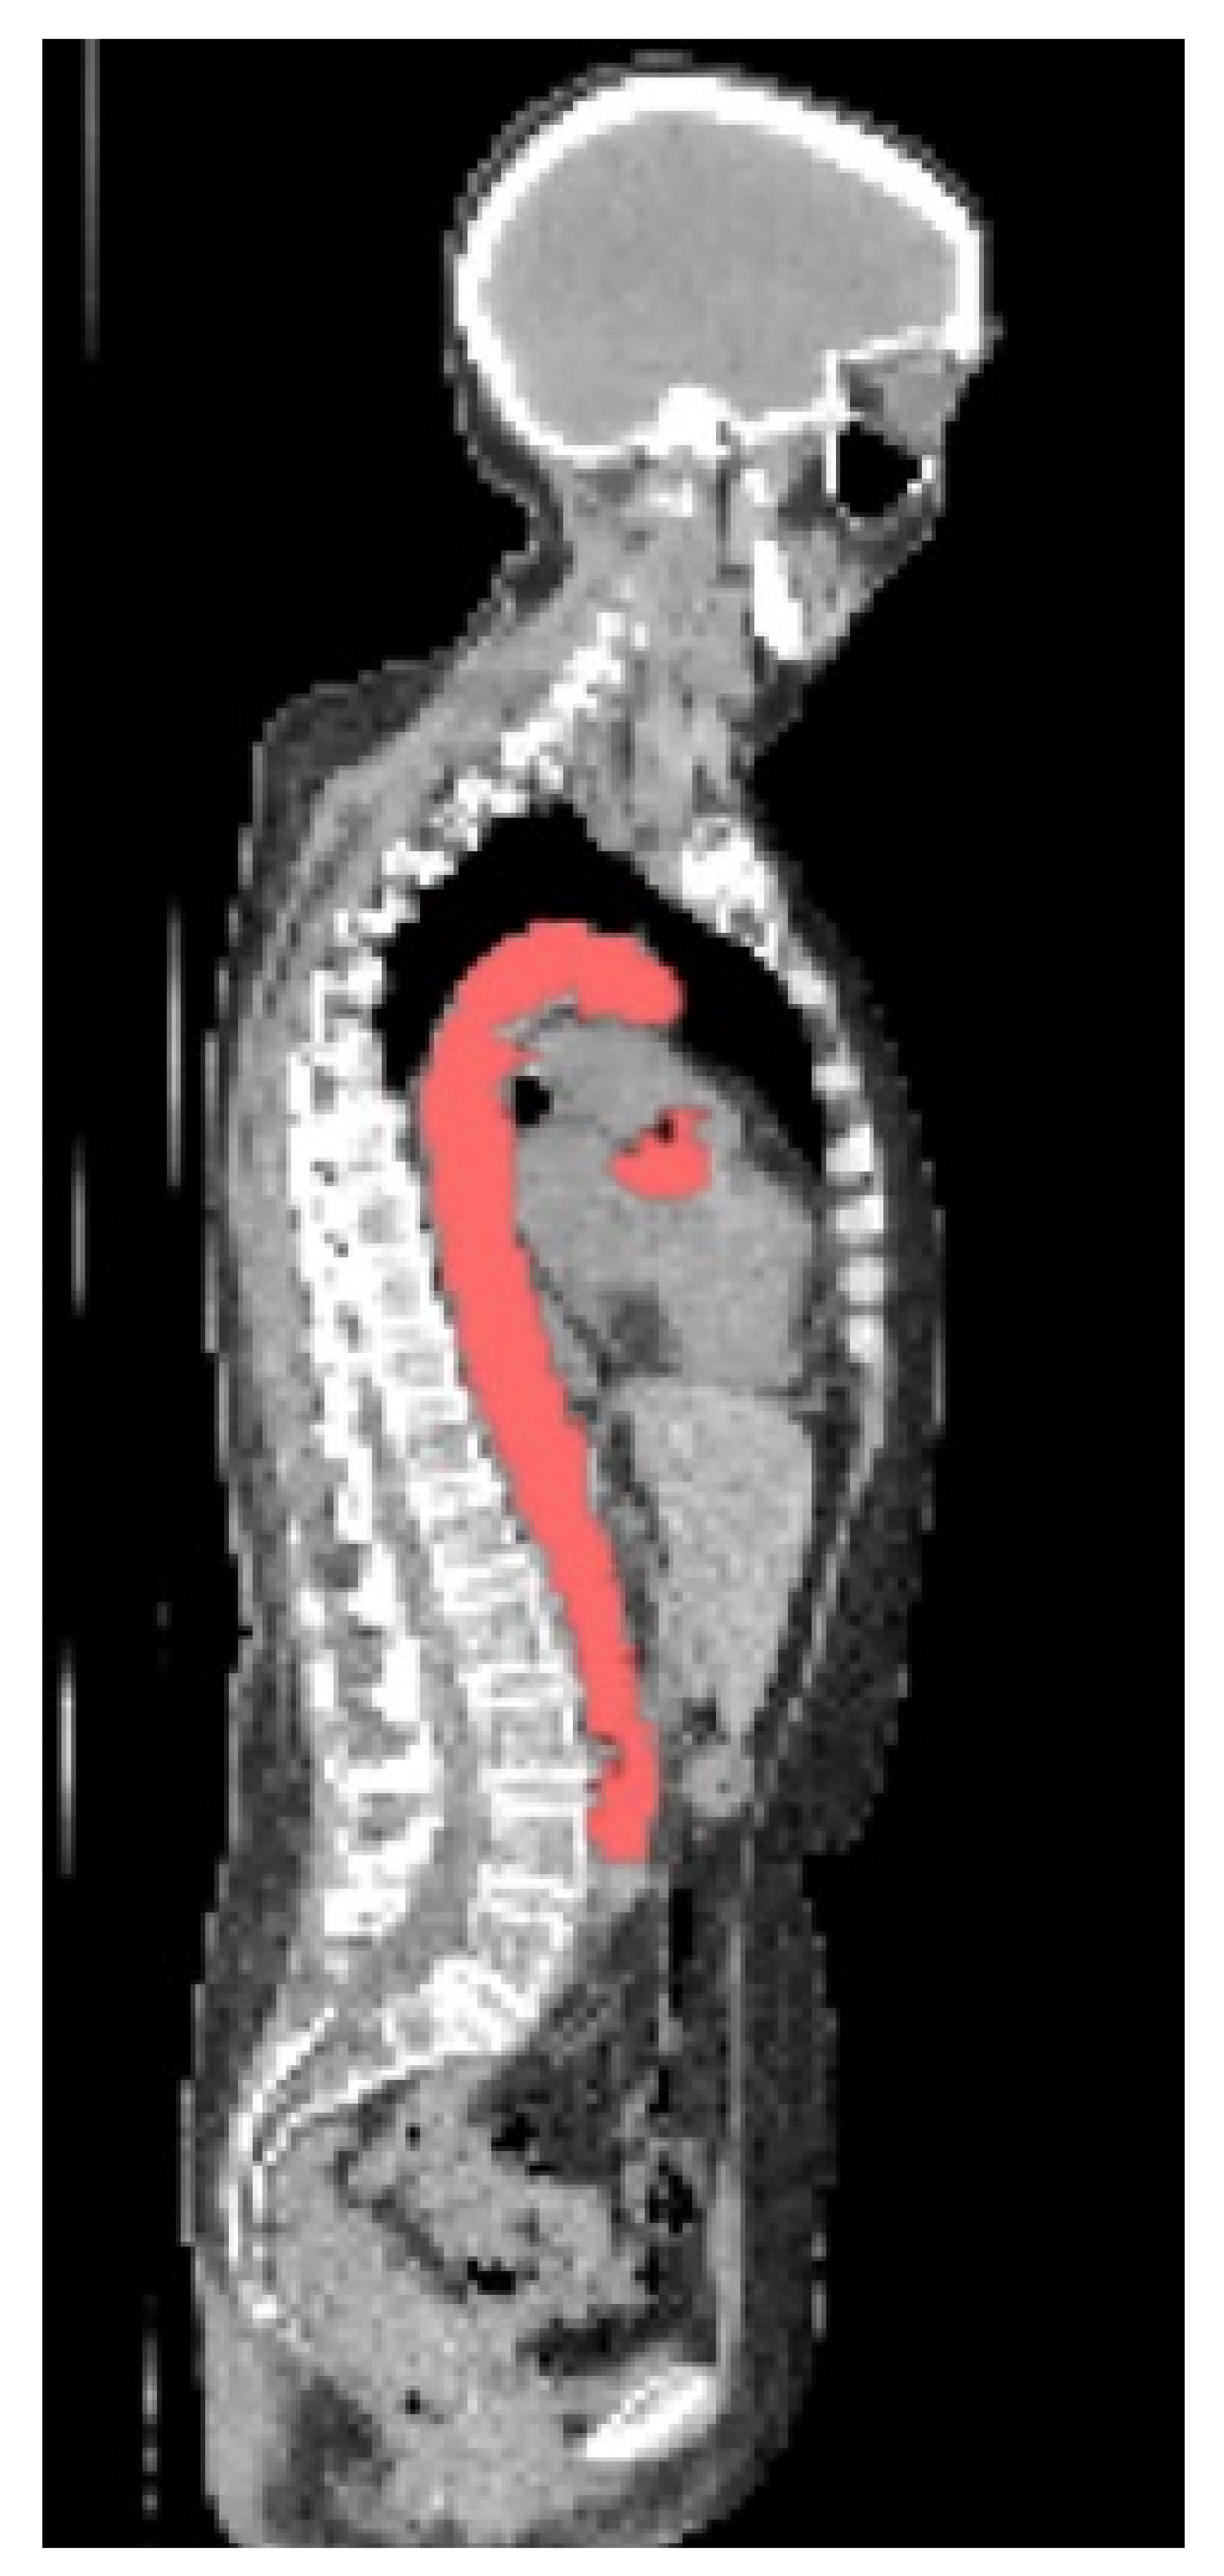

An example of a CNN segmentation is shown in Figure 4.

Figure 4.

Segmentation from CNN with small `islands’ removed.

3.2. Segmentation

The manually segmented data had a mean DSC of 0.91 when a sample was compared to segmentations conducted by a second observer. The CNN achieved a mean DSC of 0.66 (median 0.72) before small `islands’ were removed and 0.71 (median = 0.80) after when compared to the original manual segmentations used for training. The time taken to segment the aorta automatically per patient was 1 min 12 s.